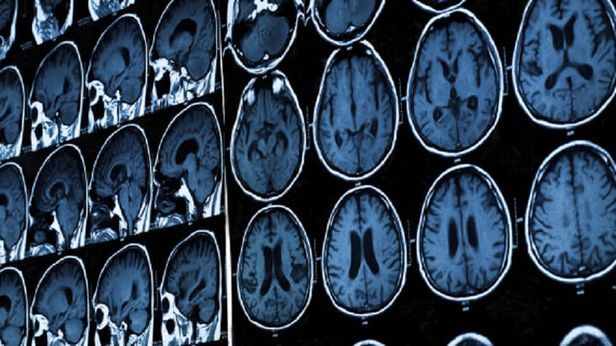

10만명 MRI 사진으로 뇌 일생 지도 완성

전 세계 10만 명 이상의 뇌 영상을 토대로 세계 최고 수준의 뇌 성장 지도가 완성됐다. 소아과에서 아이의 키와 몸무게를 재고 표준 성장도표와 비교하듯, 앞으로 뇌 발달이 또래와 다른지 확인해 뇌질환을 조기 진단할 수 있을 것으로 기대된다.

뇌 성장도표를 만들려면 수많은 사람의 뇌 영상이 필요하다. 연구진은 새로 뇌 영상을 찍는 대신 전 세계에서 진행된 뇌 연구 100여건을 이용했다. 이 방식으로 10만1457명의 뇌를 찍은 자기공명영상(MRI) 사진 12만3984장을 확보했다. MRI 영상은 수정 후 100일이 갓 넘은 태아부터 100세 노인까지 일생동안 뇌가 어떻게 변하는지 보여줬다.